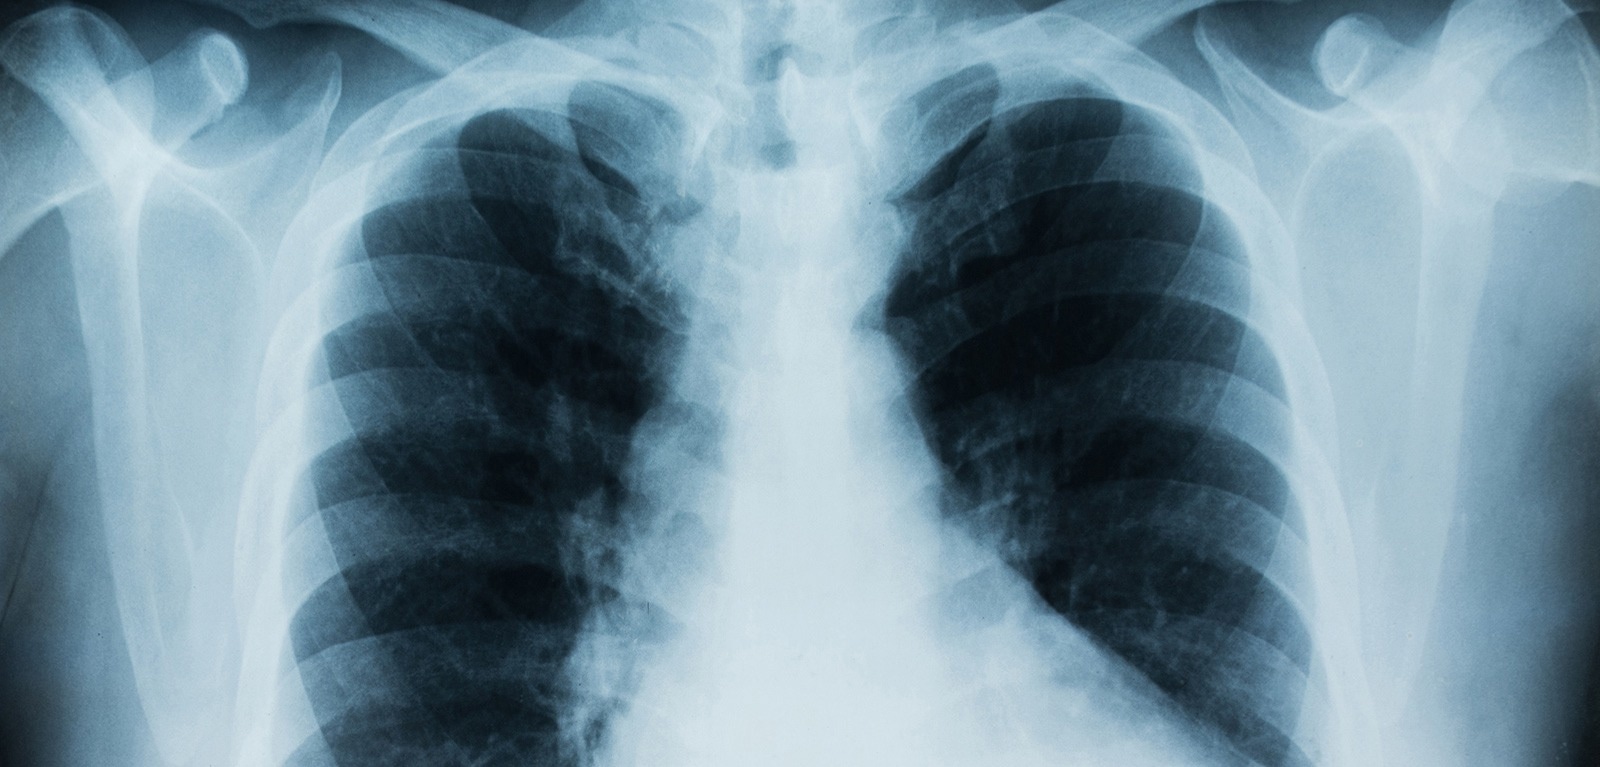

To conduct their study the researchers looked at the bacterium Achromobacter which can cause chronic lung infection and tissue damage in the airways.

The researchers observed that Achromobacter infection leads to damage in lung structure and causes severe illness if the specialized secretory pathway is functional, but not if bacteria carry mutations in the secretion system.